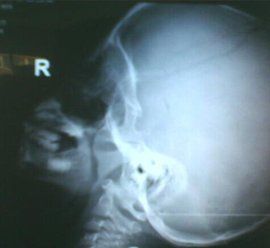

腺樣體也叫咽扁桃體或增殖體,位於鼻咽部頂部與咽後壁處,屬於淋巴組織,表面呈桔瓣樣。腺樣體和扁桃體一樣,出生後隨著年齡的增長而逐漸長大,4-6歲時為增殖最旺盛的時期,青春期以後逐漸萎縮。

在正常生理生長期,大多數孩子不會出現呼吸道梗阻的症狀,但是當腺樣體組織異常增生時,堵塞了上呼吸道,就會出現鼻堵、張口呼吸的症狀,尤以夜間加重,出現睡眠打鼾、睡眠不安,患兒常不時翻身,仰臥時更明顯。嚴重時可出現呼吸暫停,即小兒有短時間的呼吸停頓,甚至驚醒,變換睡姿後再入睡,使睡眠質量下降,同時因氣道狹窄,使血液中氧飽和度不足,大腦處於慢性持續缺氧狀態,孩子白天昏昏沉沉,精神欠佳,記憶力減退,學習成績下降。 長期鼻堵、呼吸不暢,還能影響心、肺功能,嚴重者可引起肺心病、心肌受損,甚至右室心力衰竭。由於鼻堵呼吸不暢,長期的張口呼吸還可影響頜面骨的發育,形成特殊面容,即所謂“腺樣體面容”,表現為上唇上翹,上齒外呲,上齶較高,表情呆滯。

有的患兒因鼻堵塞還可使發音受到影響,形成閉塞性鼻音,俗語稱“囔囔”聲。個別患兒還可因腺樣體肥大壓迫咽鼓管鼻咽部開口,導致中耳炎、聽力下降,因此對腺樣體肥大這種病不可輕視。如果不及時治療而形成上述疾病,如頜面畸形、肺心病等,即使切除了腺樣體,呼吸通暢了,仍需繼續長期治療其他的病症。